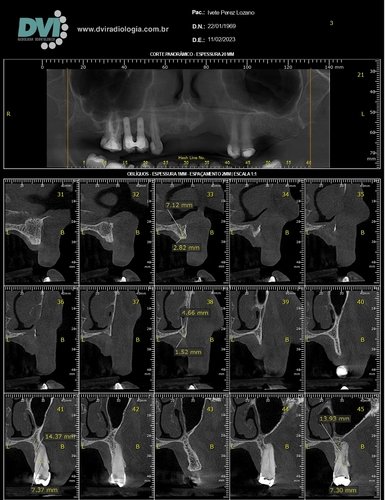

Passamos por vários especialistas e quando chegamos ao dentista da polícia militar, fomos informados que teríamos que fazer uma cirurgia para salvar o dente, cirurgia que durou em torno de 4:00 horas, mas infelizmente não foi possível salvar o dente e junto da perda do dente também tive uma perda óssea.

Entre idas e vindas no dentista para consertar o que não tinha conserto o que nunca foi explicado, para o meu pai, e depois que já não tinha mais ele, nem para mim foi explicado as condições que estava. Passados alguns anos, cai de moto, onde ao cair por cima de um carro, o capacete entrou na minha boca e terminou de quebrar o resto que tinha.

Procurando outro dentista, isso eu já mais velha, tentamos a opção de enxerto ósseo, onde meu organismo rejeitou, partimos para outra opção que eu podia fazer no momento, onde me encontro até hoje. Mas nesses dias perdi mais um dente e o restante amoleceu, e o resultado é a perda deles. Estou agora em desespero pois trabalho com crianças, falo bastante e quero muito realizar o procedimento chamado protocolo para me sentir segura ao falar, isso tem mexido bastante com minha autoestima e também a dificuldade para se alimentar, mas não tenho condição para isso, quero muito pedir a ajuda de todos(as), que sentirem de me ajudar.